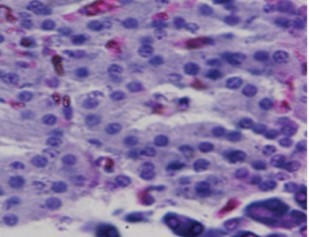

No comparable significant change observed in the mean weights of the extracted pancreas. The photomicrographs (Figure 4, Figure 5, Figure 6 and Figure 7) of the pancreatic tissue histology revealed preserved histoarchitecture in DSE and DEE groups as compared with the normal appearance of pancreas histoarchitecture from a normal healthy Wistar rat. Photomicrograph of the pancreas from diabetic control (DC) rats (Figure 7) shows distorted Islet margin with lymphocytic cells infiltration and moderate necrotic parenchyma.

Figure 5.Photomicrograph of the pancreas from DEE rats showing preserved normal pancreas histoarchitecture (H &E stain X400 magnification)

Figure 6.Photomicrograph of the pancreas from DSE rats showing preserved normal pancreas histoarchitecture (H &E stain X400 magnification)

Due to different species of garden egg in nature, likelihood of variation in its effect on weight reduction is expected. There is an uncited claim by some nutritionists that green garden egg species works better for weight loss compared to other species. However, findings obtained in our study using the white species with green stripes (S. aethiopicum L) revealed a remarkable reduction in weight gain in diabetic rats. Though, our present study did not compare species effect on weight gain, in our subsequent research however, we shall conduct a study to correlate species and weight-lowering effect. Meanwhile, based on the present outcome of this study, recommendation of the white-with-green-striped species should be encouraged for beneficial optimal effect on weight reduction. The beneficial impacts of S. aethiopicum on glycemic status and profile are depicted in Table 3 and Figure 2. The mean FBS concentrations decreased significantly (P < 0.05) in both DEE and DSE groups (DEE >> DSE, P = 0.025) compared with the control. The observed difference in their values was similar in manner to its effect on weight gain. The glycemic tolerance improved remarkably in both groups. This antidiabetic potential may be attributed to a major phenolic compound called chlorogenic acid (5-O-caffeoyl-quinic acid; CGA) present in garden egg 13, 21. Bhaskar 13 and Plazas 21 studies revealed that chlorogenic acid possessed anti-obesity, anti-inflammatory, anti-diabetic and, cardio-protective properties. The incremental areas under the glycemic response curves of DEE and DSE rats decreased remarkably compared with the control (Figure 2). The postprandial glycemic response peaked at 30 minutes of glucose challenge in both groups. The TC, TG and LDL-C concentrations decreased significantly with corresponding significant increase in HDL concentration in DEE and DSE rats (Figure 3). However, the extract impacts more beneficial antilipidemic effect than the supplemented diet. This finding also suggests that the optimal antilipidemic effect can be derived when S. aethiopicum is consumed in fresh or raw form than in mixed meal. The antilipaemic effect of eggplants has been attributed to an important phytonutrient compound called anthocyanin found in abundance in the skin of the eggplant which was reported to improve lipid profile through lipid peroxidation and serum antioxidants concentrations increase 27. Besides this antilipaemic activity, anthocyanin has also been reported to play significant role against diabetes, neuronal problems, cardiovascular disorders, and cancer as well 30. The pancreatic tissues sections’ photomicrographs examined under high power magnification (x 400) light microscope revealed the effects of S. aethiopicum on pancreas histoarchitecture. Figure 4 shows the normal appearance of the pancreatic histoarchitecture obtained from a healthy non-diabetic Wistar rat. Comparison of the experimental grouped rats photomicrographs with the normal revealed that the histoarchitecture of the pancreas in DEE and DSE (Figure 5, Figure 6) rats were preserved with no visible pathologic changes while the photomicrograph of the pancreas from diabetic control (DC) rats (Figure 7) shows distorted Islet margin with lymphocytic cells infiltration and moderate necrotic parenchyma. Examining the histological consequence of any product prior to recommendation is very essential because histological analysis of target organs for pathological changes surveillance is necessary to enhance screening assessment of quality and safety of product prior to recommendation for human consumption 31